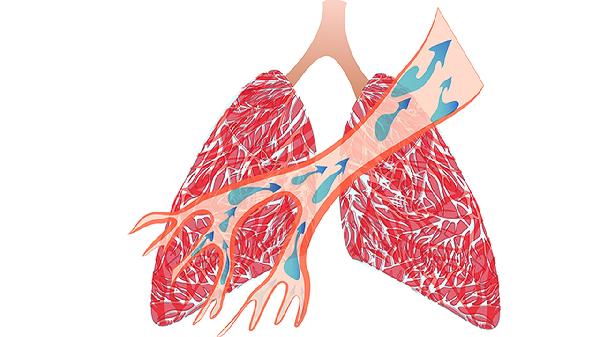

冬天一到,冷空氣就像個愛搞惡作劇的調皮鬼,專挑呼吸系統下手。不少人開始咳嗽、喉嚨發幹,甚至體檢報告上突然冒出”肺結節”三個字。這時總有人推薦百合潤肺,但你可能不知道,有種更厲害的養肺食材正躲在菜市場角落偷笑。

白蘿蔔中的芥子油苷會在體內轉化為蘿蔔硫素,這種物質能啟動肺部細胞的自我保護程式。就像給肺細胞穿上隱形防護服,既減少外界刺激,又降低異常增生的風險。